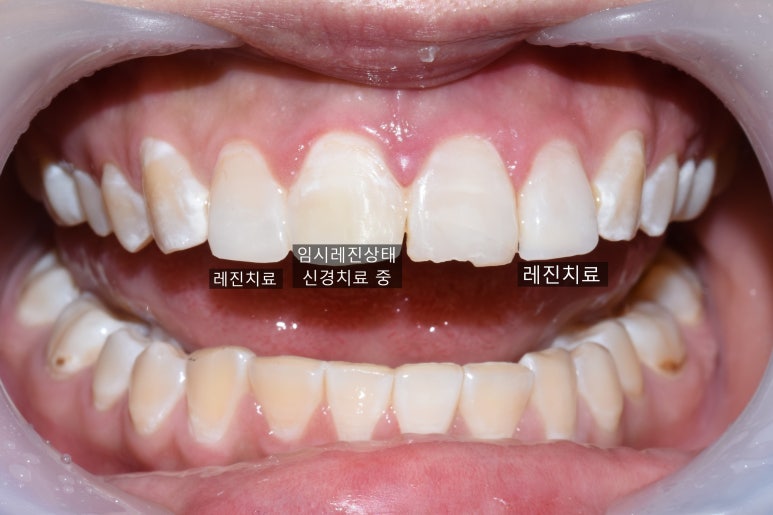

다른 치과에서 발치 설명들은 치아는 일단 임시로 레진으로 떼우고

신경치료 진행중이며, 다른 나머지 치아들은

![[서대문가까운/치과] 깨진 치아 레진 떼운 사례 관련 이미지 4](https://pub-9f2bb3498faf4d1d8714b41df24753e3.r2.dev/content/clinics/archive/rseeanjxfu/naver_blog/yonseiyegam/assets/by_hash/b935a012a28da77b93f2b53168e0456f9790c655963f4eb108943dc22dd3ed9d.jpg)

위와 같이 4개치아 중 양 가쪽 2개는 레진으로 떼워놓은 상태입니다.

환자분이 깨진 것 떼우는 김에 길이도 더 길게 하고 싶어하셔서 길게 해드리고

치아색도 조금 더 자연스럽게 하얗게 해드렸더니 좋아하고 만족하셨습니다.

처음 → 치료중(레진치료 2개완료와 임시레진상태로 신경치료 중)

좌우 차이가 느껴지시나요?

현재 신경치료 중인 치아는 예후를 봐서

앞으로 어떻게 할지 결정할 예정이며

환자분이 다른 깨진 앞니도 치료받고 싶다고 하셨습니다!